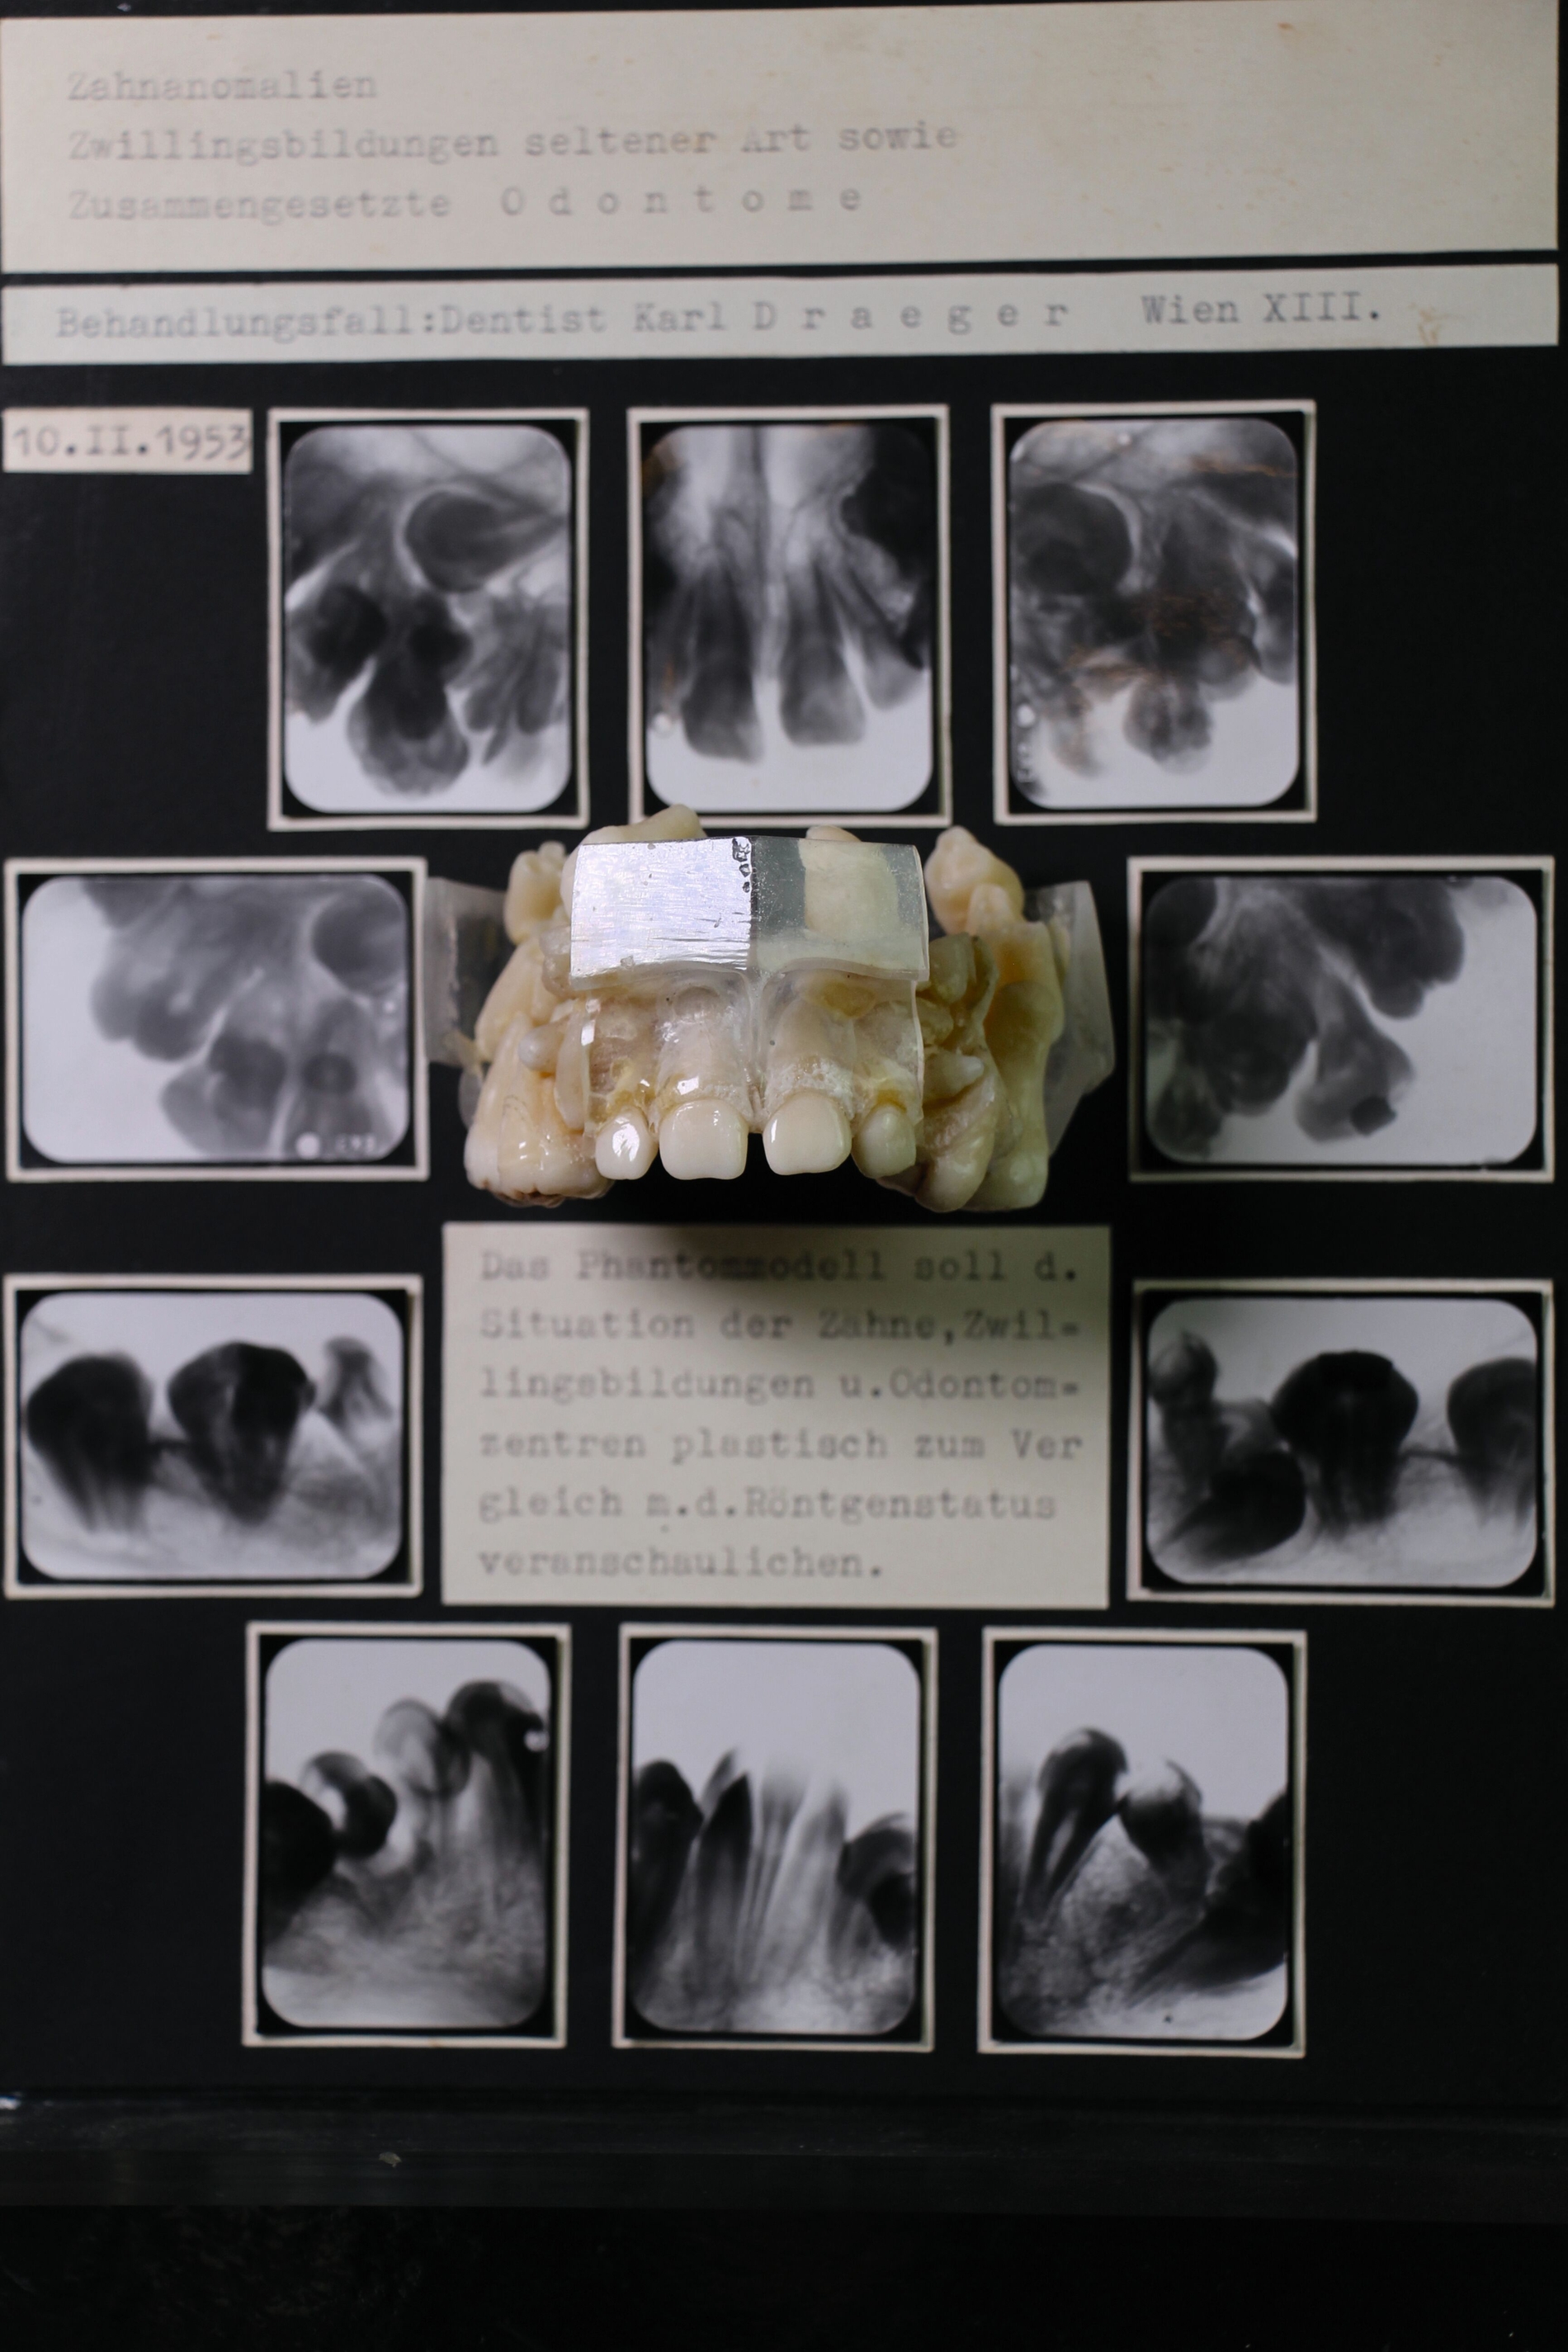

Wer sich ein bisschen feiner erinnern will, findet etwa den Dreiseiter „Der Beruf des Dentisten in der Zahnheilkunde“ von Kirstin Zähle aus 2006, bebildert mit Exponaten aus dem Dentalmuseum, unter anderem mit einer Schautafel aus der Sammlung Draeger. Dort arbeitet sie heraus, wie sich die Dentisten von (zuerst fachfremden) groben Handwerkern zu einer professionellen Berufsgruppe entwickelt haben, seit 1920 mit staatlicher Dentisten-Prüfung nach zweijähriger Fachschullehre – ohne medizinisches Wissen. Und wie sie dennoch zu einer Säule der Versorgung wurden, da sie oft „dieselben Behandlungen“ durchführten. Und wie in der Folge die „große Kluft“ zu den studierten Zahnärzten entstand. Und wie nach dem Krieg der Konflikt und Dualismus überwunden wurden: Mehr als 15.000 Dentisten buchten bis Ende 1953 den erforderlichen 60-stündigen Fortbildungskurs, um Zahnarzt zu werden. Lange her.

Jedenfalls wird auch Karl Draeger, er lebte in Wien, eine solche Ausbildung durchlaufen haben, bevor er „vermutlich selbst in der Dentistenausbildung tätig wurde“, sagt Museumsleiter Andreas Haesler. Auch wenn detaillierte Lebensdaten fehlen, kann er aus Draegers Korrespondenz die Entstehung der Schautafeln auf etwa 1925 bis 1975 datieren. Ausgehend von Röntgenbildern, die ihm „aus halb Europa“ geschickt wurden, hat Draeger über Jahrzehnte die Tafeln mit den Zahnanomalien nachgebaut, anfangs (bis etwa 1950) montierte er sie auf Pappe, später auf Glas.

Haesler sagt: „Ich bewundere diese einzigartige handwerkliche Präszisionsarbeit. Und den Fleiß.“ Stundenlang könne er sich ansehen, wie Draeger die damals bekannten Krankheitsbilder für die studentische Ausbildung nachgebaut und damit anschaulich gemacht hat. Für ihn Ausweis der hohen Qualität der dentistischen Ausbildung. Insgesamt sind es über 15.000 Zähne, verteilt auf über 1.000 Tafeln.